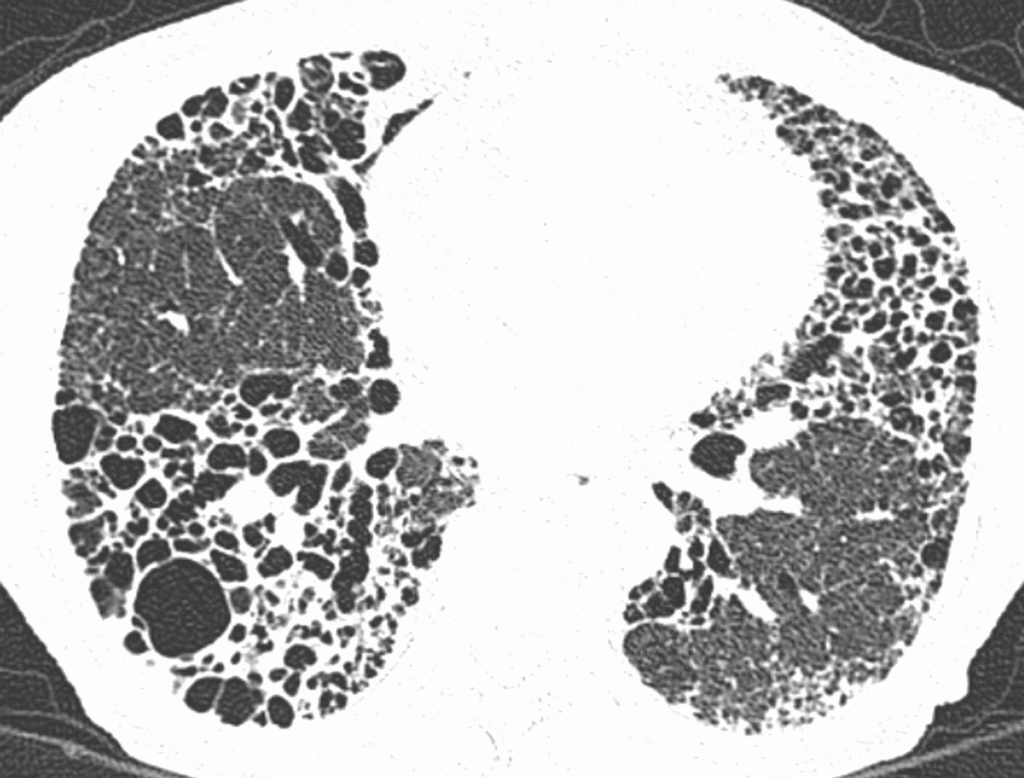

- HRCT (Goldstandard): „honigwabenartige“ Veränderungen (v. a. bei IPF)

| Idiopathische Lungenfibrose (IPF) | unklar (idiopathisch) | Belastungsdyspnoe, trockener Husten, Trommelschlegelfinger | HRCT: Honigwaben, basal, subpleural; Lufu: restriktiv | Antifibrotika(Pirfenidon, Nintedanib), evtl. Lungentransplantation | Respiratorische Insuffizienz, pulmonale Hypertonie |